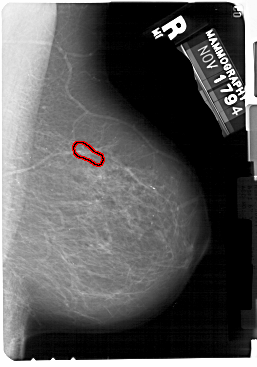

A_1175_1.RIGHT_MLO

RIGHT_MLO LINES 5491 PIXELS_PER_LINE 3841 BITS_PER_PIXEL 12 RESOLUTION 43.5 OVERLAY

FILE: A_1175_1.RIGHT_CC.OVERLAY

TOTAL_ABNORMALITIES 1

ABNORMALITY 1

LESION_TYPE CALCIFICATION TYPE PLEOMORPHIC DISTRIBUTION LINEAR

ASSESSMENT 4

SUBTLETY 3

PATHOLOGY MALIGNANT

TOTAL_OUTLINES 1

BOUNDARY